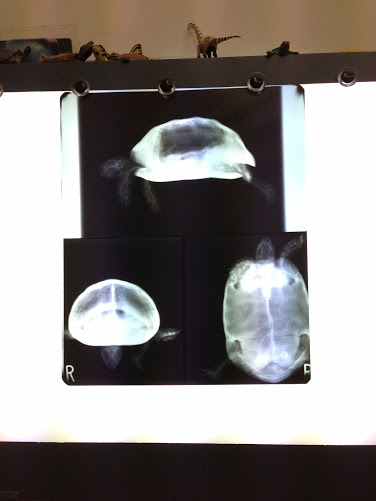

横から見たところ、前からみたところ、下から見たところのレントゲン写真

結石などの心配をしていたのですが、特に問題なしとのこと。

しかしながら一点おかしなところが・・・

それは、下の写真です。

真ん中に黒い部分がありますが、これは肺です。

その下の白い部分が右斜め上になだらかに上がっていると思いますが、

ここが腸らしいです。

本来ならこの腸がもっと張りがあるというか、うねっているらしいです。

この写真をみるかぎり腸が働いていないとのこと。